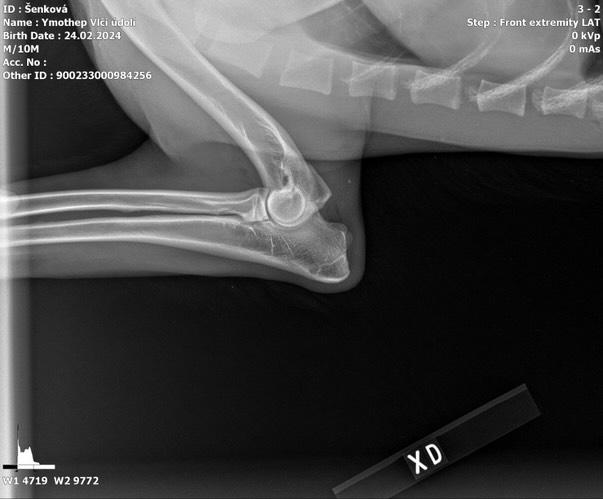

DOB: 02/24/24